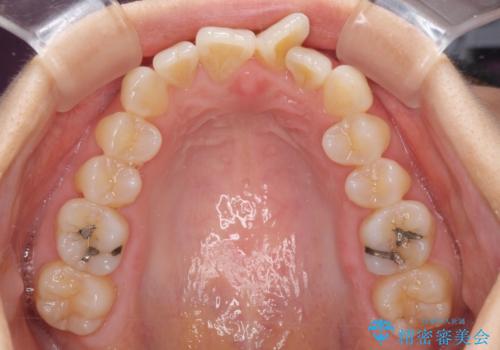

短期間で仕上げたい ワイヤーでの非抜歯矯正

- 前歯の捻れと、それに伴う口元の突出感を気にして来院された患者様です。

早く治療を終えたいとのことで、ワイヤー装置による矯正治療を行うこととしました。

上顎前歯の叢生が解消されると出っ歯になることが分かっていたので、両側奥歯付近にアンカースクリューを入れ、出っ歯を改善するためのゴムかけを行いました。

ゴムかけを頑張っていただいたので、当初の予定通り、1年強で治療を終えることができました。